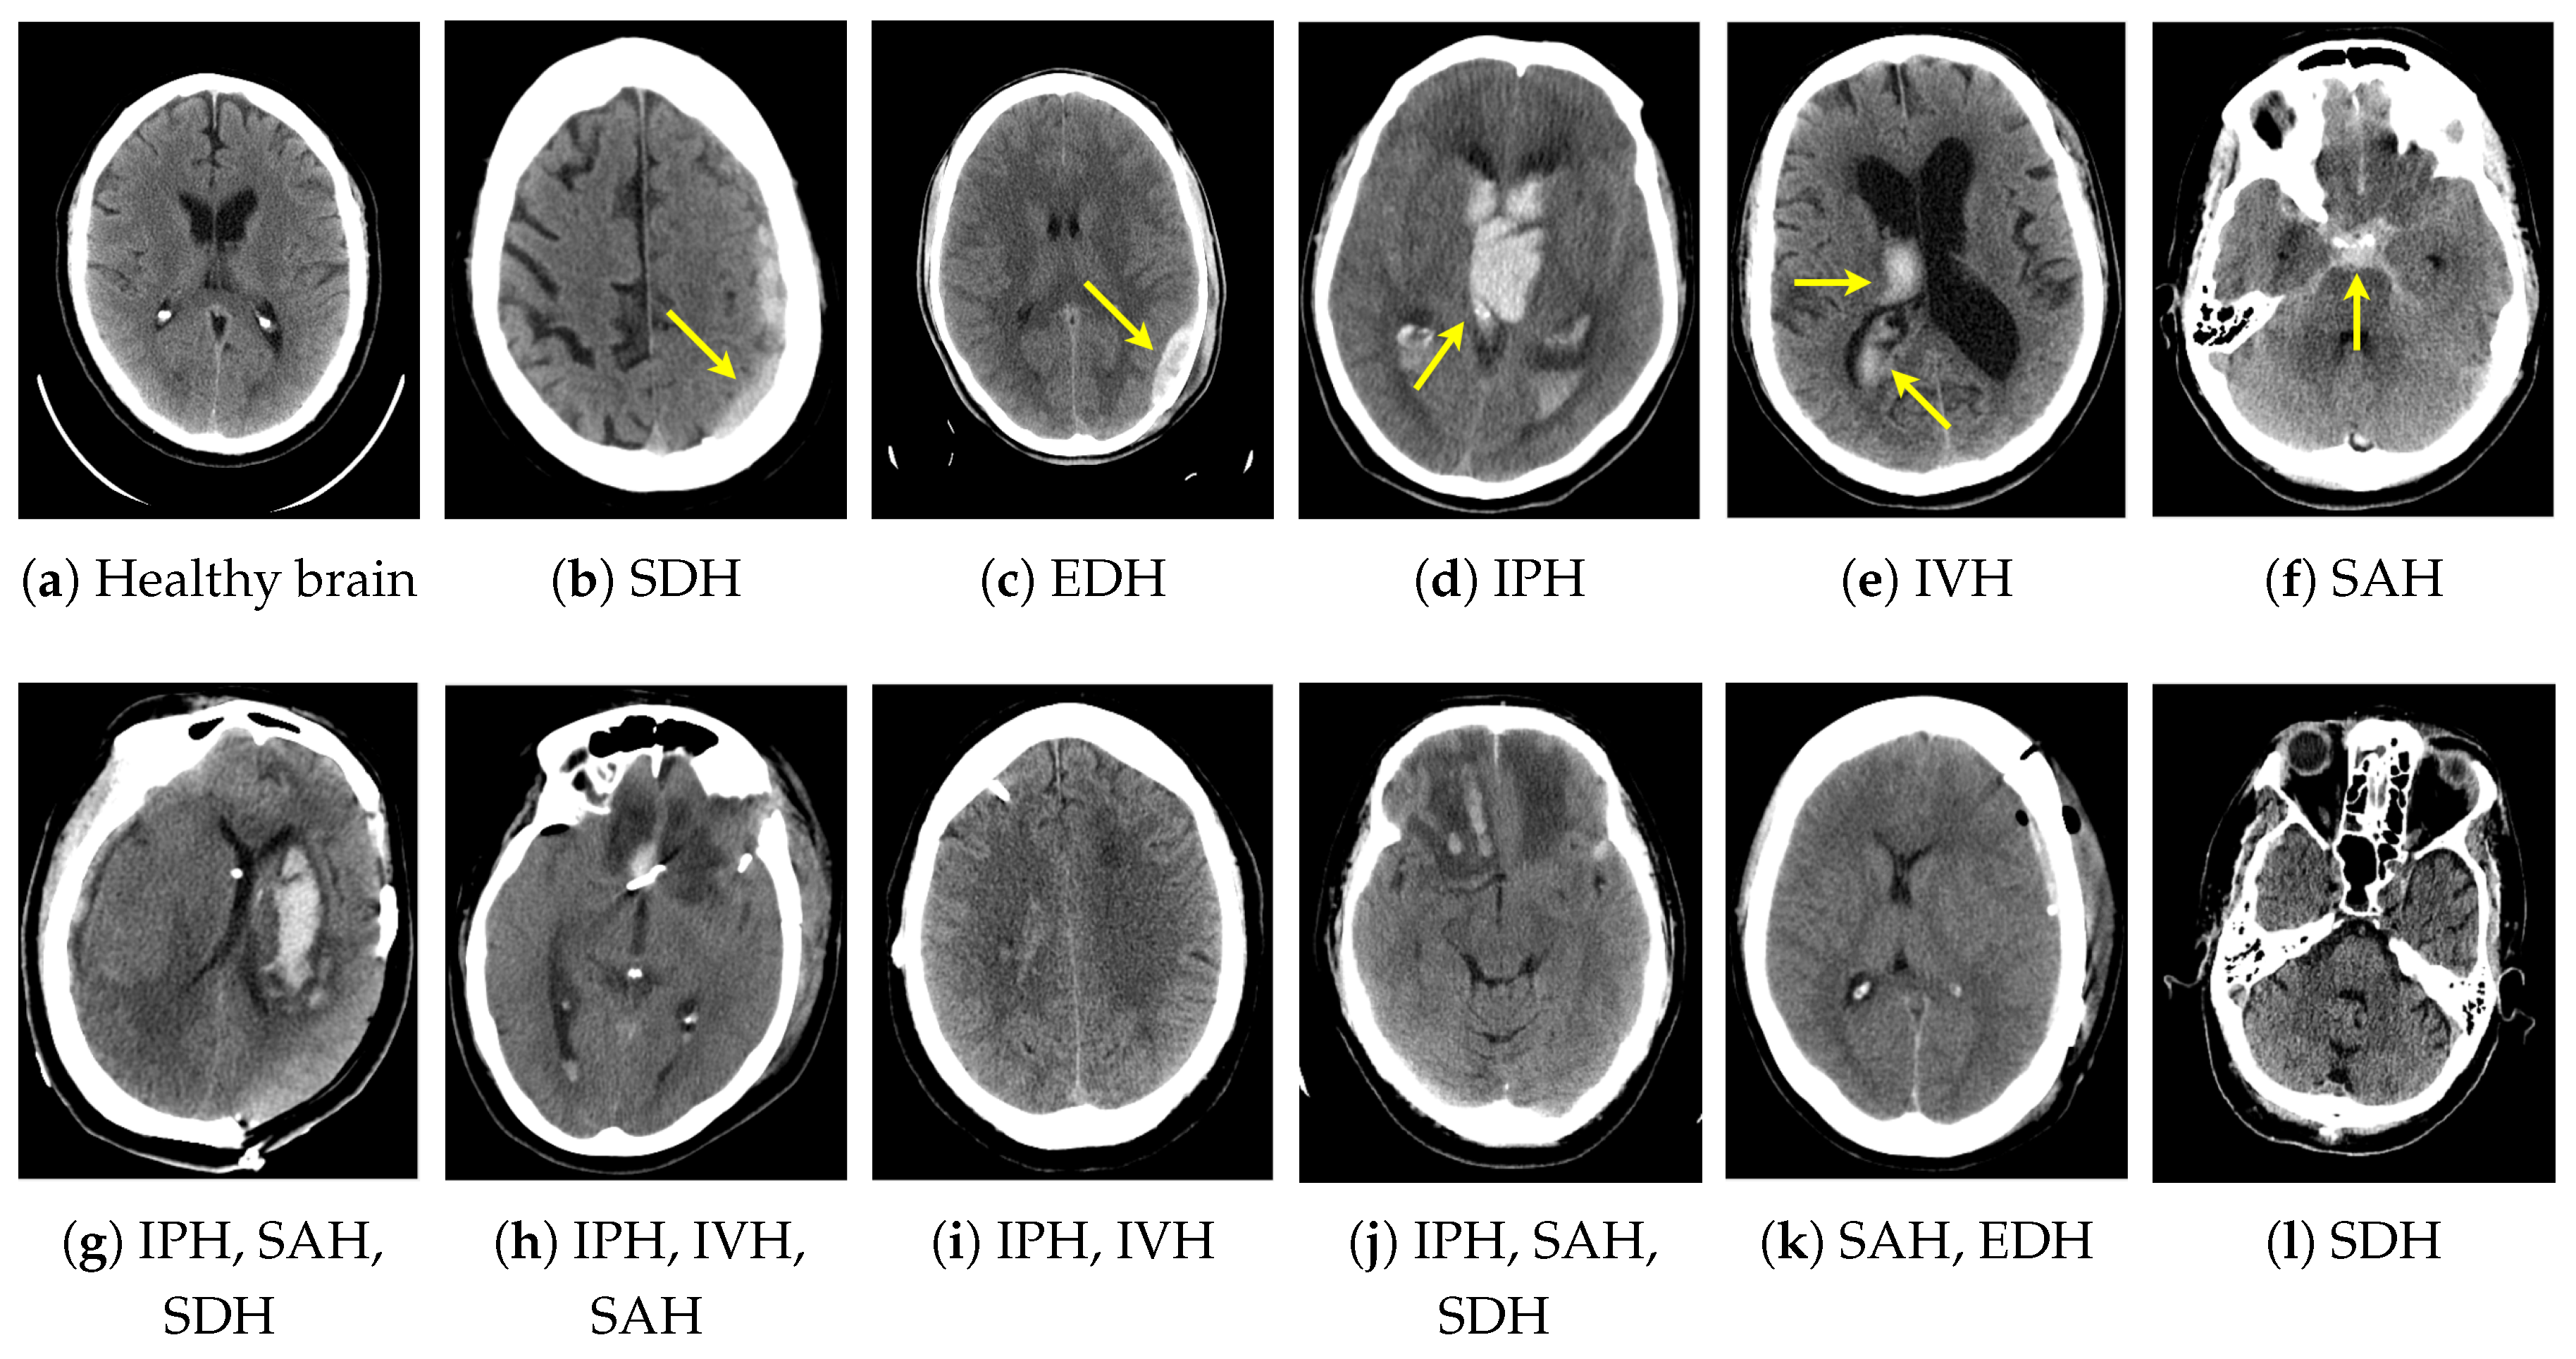

From www.mdpi.com

Applied Sciences Free FullText Intracranial Hemorrhage Detection Is Ct Head Same As Ct Brain This procedure is noninvasive, meaning it doesn’t require. A cranial ct scan is known by a variety of names as well, including brain scan, head scan, skull scan, and sinus scan. Computed tomography (ct) scans of the head are an important diagnostic tool in modern medicine, offering detailed images of. A ct scan of the head can provide more. Magnetic. Is Ct Head Same As Ct Brain.